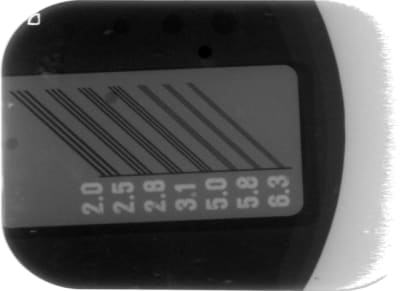

voilà ce qu'il faut montrer pour comparer 2 systèmes radios + capteurs

image jointe = capteur owandy DSX730 et gén X GENDES X-Mind system

le reste c'est de la photo de "paysage" sans aucune comparaison possible

C'est encore mieux avec une grille effectivement et moi non plus je n'arrive pas à envoyer une PJ sur Eugenol

ici une pano sirona

on voit les paires de lignes à 3,1 paires de lignes / mm alors que l'acceptable est à 2,5

et ce n'est qu'une photo d'ecran ...donc les 4 trous de basse résolution sont difficiles à photographier